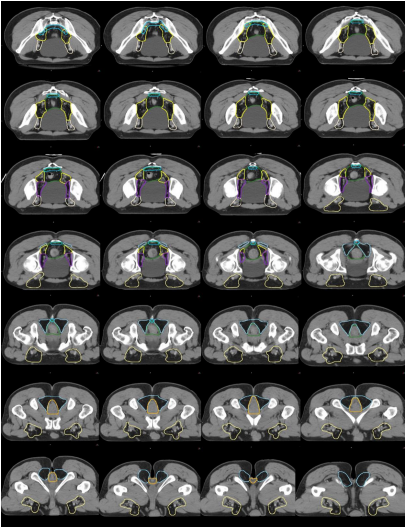

f) 腹股溝淋巴引流區(qū)-IN(黃褐色) (圖 11)邊界:

上界:旋髂深靜脈與髂外動脈交叉處或者髖臼頂部與恥骨上支連接之處;

下界:大隱靜脈匯入股靜脈處/坐骨結(jié)節(jié)下緣;

前界:腹股溝血管周圍向前至少 2 cm,包括所有可見的淋巴結(jié);

后界:由髂腰肌、恥骨肌和長收肌圍成的股三角;

內(nèi)界:腹股溝血管周圍至少 1~2 cm,包括所有可見的淋巴結(jié);

外界:縫匠肌或髂腰肌內(nèi)側(cè)緣。

圖 11 直腸癌腹股溝淋巴引流區(qū) CTV 勾畫示例

g) 坐骨直腸窩-IRF(天藍(lán)色) (圖 12)邊界:

上界:下陰部動脈離開盆腔處;

下界:肛門括約肌復(fù)合體下緣和坐骨結(jié)節(jié)的虛擬斜面;

前界:閉孔內(nèi)肌和肛門外括約肌圍成;

后界:中/上:臀中?。幌拢和未蠹?nèi)緣的虛擬連線;

內(nèi)界:肛門外括約肌;

外界:上/中:閉孔內(nèi)??;下:坐骨結(jié)節(jié)、臀大肌。

h) 肛門括約肌復(fù)合體-SC(桔色) (圖 13)邊界:

上界:肛提肌插入肛門外括約肌處/直腸肛管交界處;

下界:放松位的肛門緣;

前界、后界、內(nèi)界、外界:肛門外括約肌圍成。

圖 12 直腸癌坐骨直腸窩 CTV 勾畫示例

圖 13 直腸癌肛門括約肌復(fù)合體 CTV 勾畫示例

i) 高危復(fù)發(fā)區(qū)合集圖(CT 層厚 0.5 cm,俯臥位)(圖 14)。下表 示出高危復(fù)發(fā)區(qū)顏色。

表 直腸癌高危復(fù)發(fā)區(qū)顏色

圖 14 直腸癌高危復(fù)發(fā)區(qū)合集圖